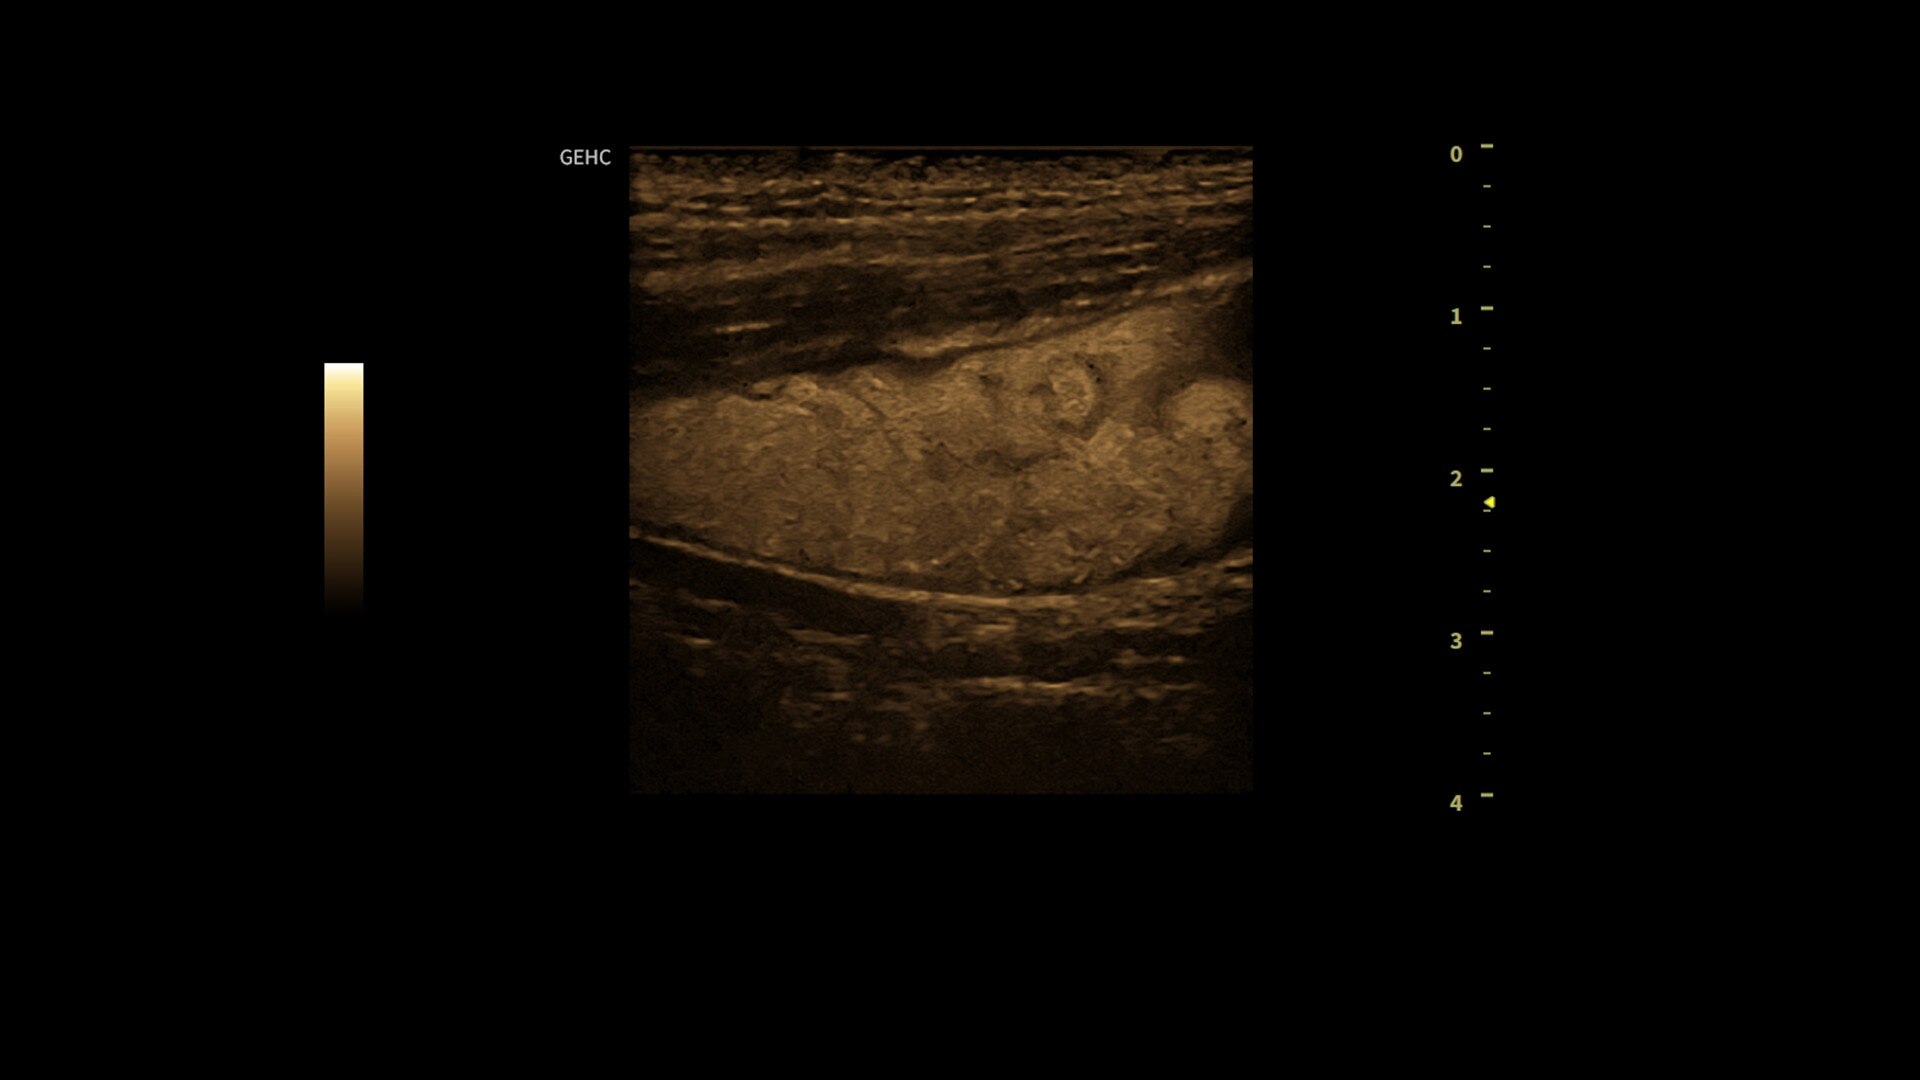

• Optimize images while scanning with Whizz clinical features, easily improve Color Doppler with Whizz Color Flow, and view scans in the image style that suits your preference with Whizz Easy Style

• Make automated 2D Measurements and Volume Calculations with Auto Contour, Auto Bladder, Whizz Follicle and Auto-IMT

• Assess liver, thyroid and breast nodules with Productivity Packages leveraging LI-RADS,® TI-RADS® and BI-RADS® criteria*